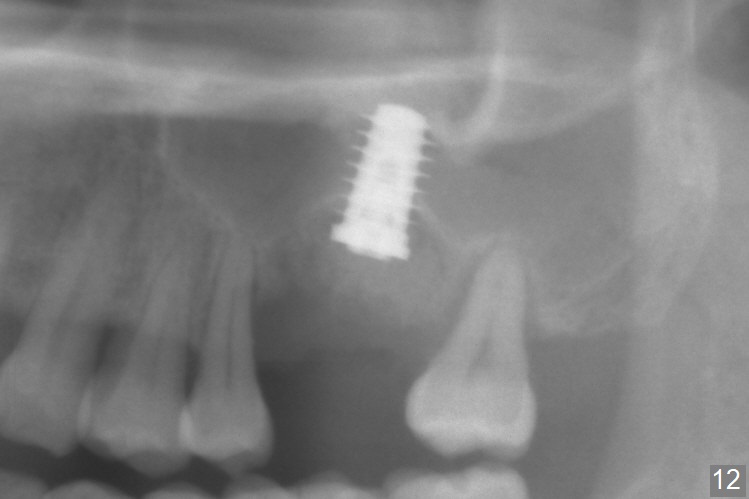

When the displaced tooth #14 (Fig.1) with palatal gingival recession (Fig.2) is extracted, the buccal plate is low, while the palatal one is lost.  Osteotomy is initiated in the bottom of the large socket with Marking Drill.  The bone turns bluish, suggesting thin bone (in fact less than 1 mm as well as low density).  Magic Sinus Lifter (Fig.3 *, Fig.4 blue area) is used for sinus lift (Fig.4 (red curved line: lifted sinus membrane; grey area: a portion of the lifted sinus floor), followed by insertion of a piece of PRF plug and Vanilla bone graft for sinus lift.  The osteotomy is enlarged lightly with 4.8 mm Magic Drill (compare black strips between Fig.4,5).  A 5x9 mm dummy implant (Fig.5 green) is dislodged into the sinus.  The lifted sinus membrane holds the implant in place.  The black thin strip in Fig.5 and black circle in Fig.6a (occlusal view) represents the osteotomy.  After increase in the osteotomy with Lindamann bur (Fig.6b red circle), the implant (Fig.6c green) is retrieved with endodontic forceps (Fig.6c two blue dots (beaks of the forceps); Fig.7,8).  With the enlarged osteotomy (Fig.6d), a 6x9 mm dummy implant is placed deep (Fig.9).  The definitive implant is 6.5x11 mm with insertion torque ~ 15 Ncm (Fig.10).  With placement of a healing screw and further placement of allograft (Fig.11 *), the socket is closed with PRF membrane and collagen plug (Fig.12).

Poor visibility for immediate implant in the molar region is another contributing factor for the dislodgement.  The patient returns for follow up 15 days (Fig.15) and 1 month (Fig.16) postop.  Bone graft seems to be stable around the implant.  The socket heals 4 months postop (Fig.20).  The implant seems to have been osteointegrated (Fig.17,18).  It will be backed up for ~ 3 mm to improve implant/crown ratio (Fig.19, as compared to Fig.14).  If it cannot be done, take impression immediately and make a subgingival provisional before suturing.

In fact, there is no coronal bone for the implant to be backed up.  Therefore, impression is taken after uncover and insertion of a 5.5x5.7(4) mm abutment.